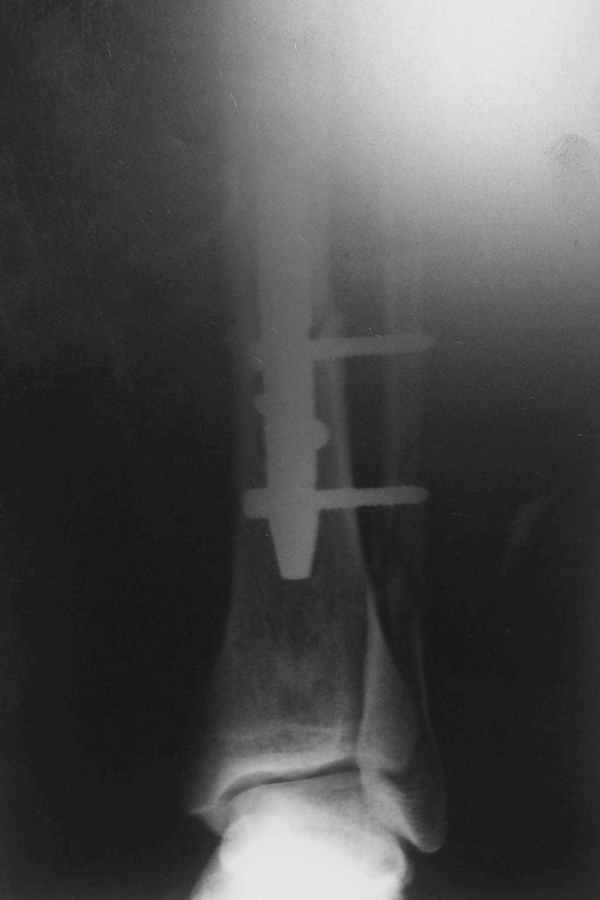

Перелом спиральный, то есть низкоэнергетический, так что со сращением дело обстоит уже неплохо, лишь бы "костоеда" не развилась. Отломки выглядят уже стабилизированными костной мозолью, так что довводить винты, наверно, уже незачем. Разве что при клинической оценке подвижность еще есть - тогда можно для стабилизации наложить простейший аппарат, не опасаясь контакта его элементов с гвоздем, поскольку места в дистальном метафизе оставлено более чем достаточно.

С Александром согласен, нет необходимости делать дополнительные усилия для сращения, не большая компрессия аппаратом из двух колец и полная нагрузка доделает работу.

Удалять их всё равно придётся.

Уже имеется какое-то сращение. А в этих условиях выполнить реостеосинтез гвоздём не дольше, чем "накинуть" аппарат из двух колец. Ходить можно сразу с полной нагрузкой, да и качество жизни пациента без аппарата лучше.